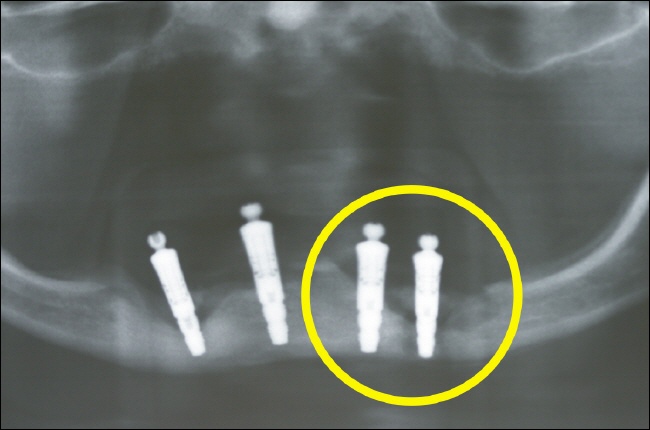

Fehlende Nachkontrollen und Röntgenkontrollen können dazu führen, dass ein massiver Knochendefekt um Implantate herum auftritt, ohne dass der Patient davon etwas merkt. Dies kann sogar im ungünstigsten Fall dazu führen, dass die Unterkieferspange so stark geschwächt ist, dass sie den normalen Belastungen nicht mehr standhält und es zu einer Kieferfraktur kommt.

Heftiger Knochenabbau (Risiko Kieferfraktur) Das Röntgenübersichtsbild zeigt nichts Gutes. Die dunklen Bereiche um die Implantate (helle "Stifte") spiegeln den daramtischen Knochenabbau wieder. Besonders am ganz rechten Implantat (gelber Kreis) reicht dieser Knochenabbau schon durch den gesamten Unterkeiferkörper. Es besteht hierbei ein sehr hohes Risiko für eine entzündungsbedingte Kieferfraktur (sog. pathologische Fraktur).